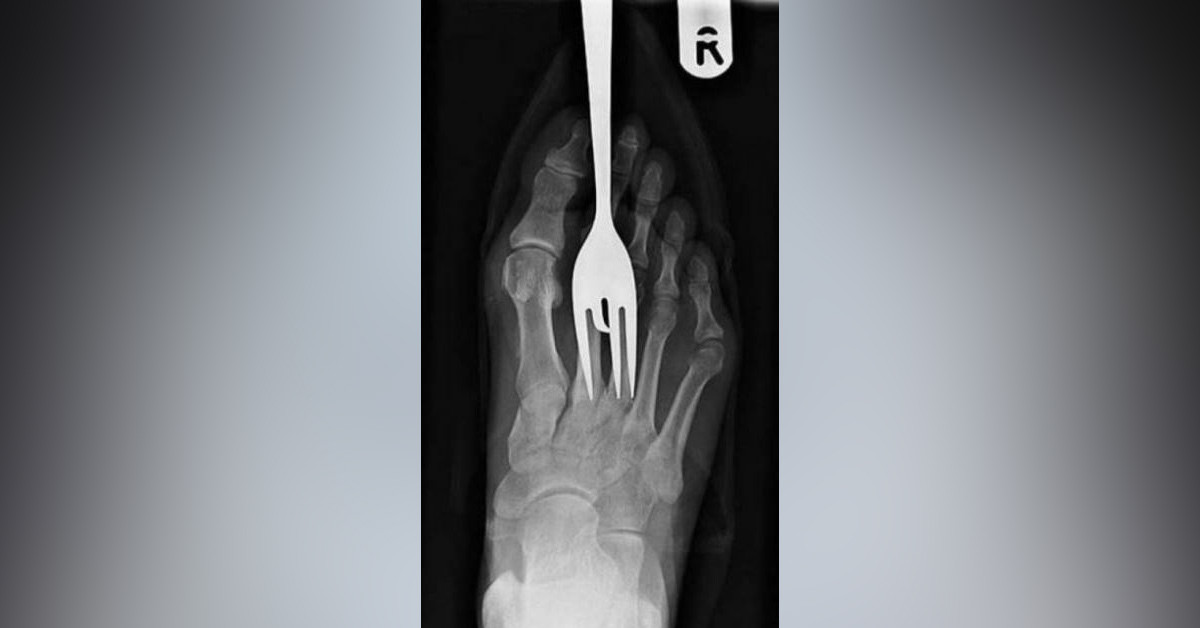

Törpünün orada ne işi var?